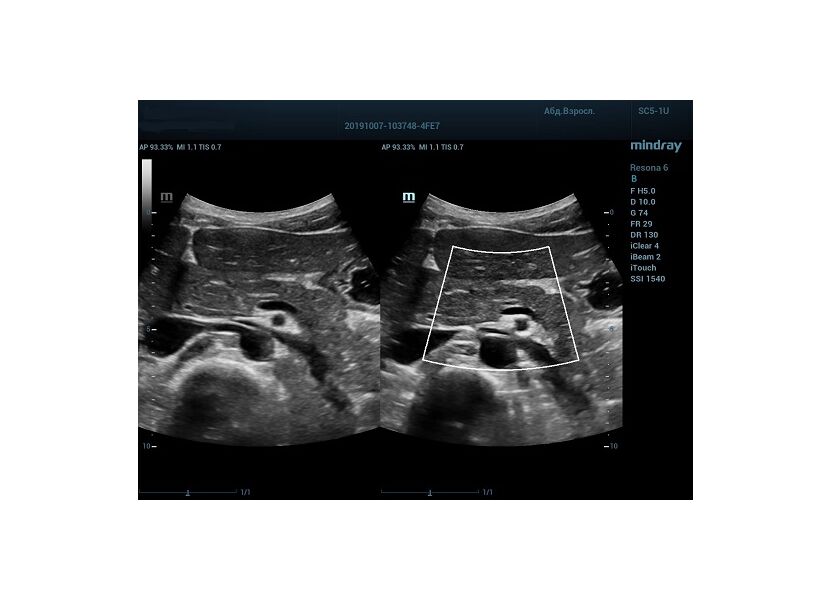

HD Scope позволяет достигать поразительной разрешающей способности выбранной зоны сканирования, при этом улучшая как детализацию, так и контрастность изображения. Помимо пространственного разрешения мы получаем преимущество и по разрешению во времени. Прибор получает огромное количество нативных изображений практически одновременно, и при сборе итоговой картины не происходит смещения объекта под датчиком, а значит и нет размывания изображения. Все участки раздела фаз, каждый контур образования теперь видны, мы все ближе к идеальной картинке.

Как он работает? Особенностью платформы ZST+, на которой построены приборы Mindray Resona, является так называемое многолучевое сканирование. В отличие от обычного датчика, который получает изображение в виде прямого эхо, датчики приборов этой серии проводят многолучевое сканирование каждым элементом с огромной скоростью, получая огромное количество данных. Затем происходит сложная постобработка и сбор из множества «многолучевых» снимков идеальной картинки.

Вторая особенность ультразвуковых машин данной линейки — это изменение расчетных констант распространения ультразвука, таким образом прибор перебирает для каждой ткани свои значения скоростей волны и пересчитывает каждую точку, делая менее выраженным поглощение по глубине. Эти особенности позволили использовать без фокусные технологии сканирования. Функция HD Scope позволяет использовать эти ресурсы для исследование небольшой области, значительно увеличивая качество изображения.